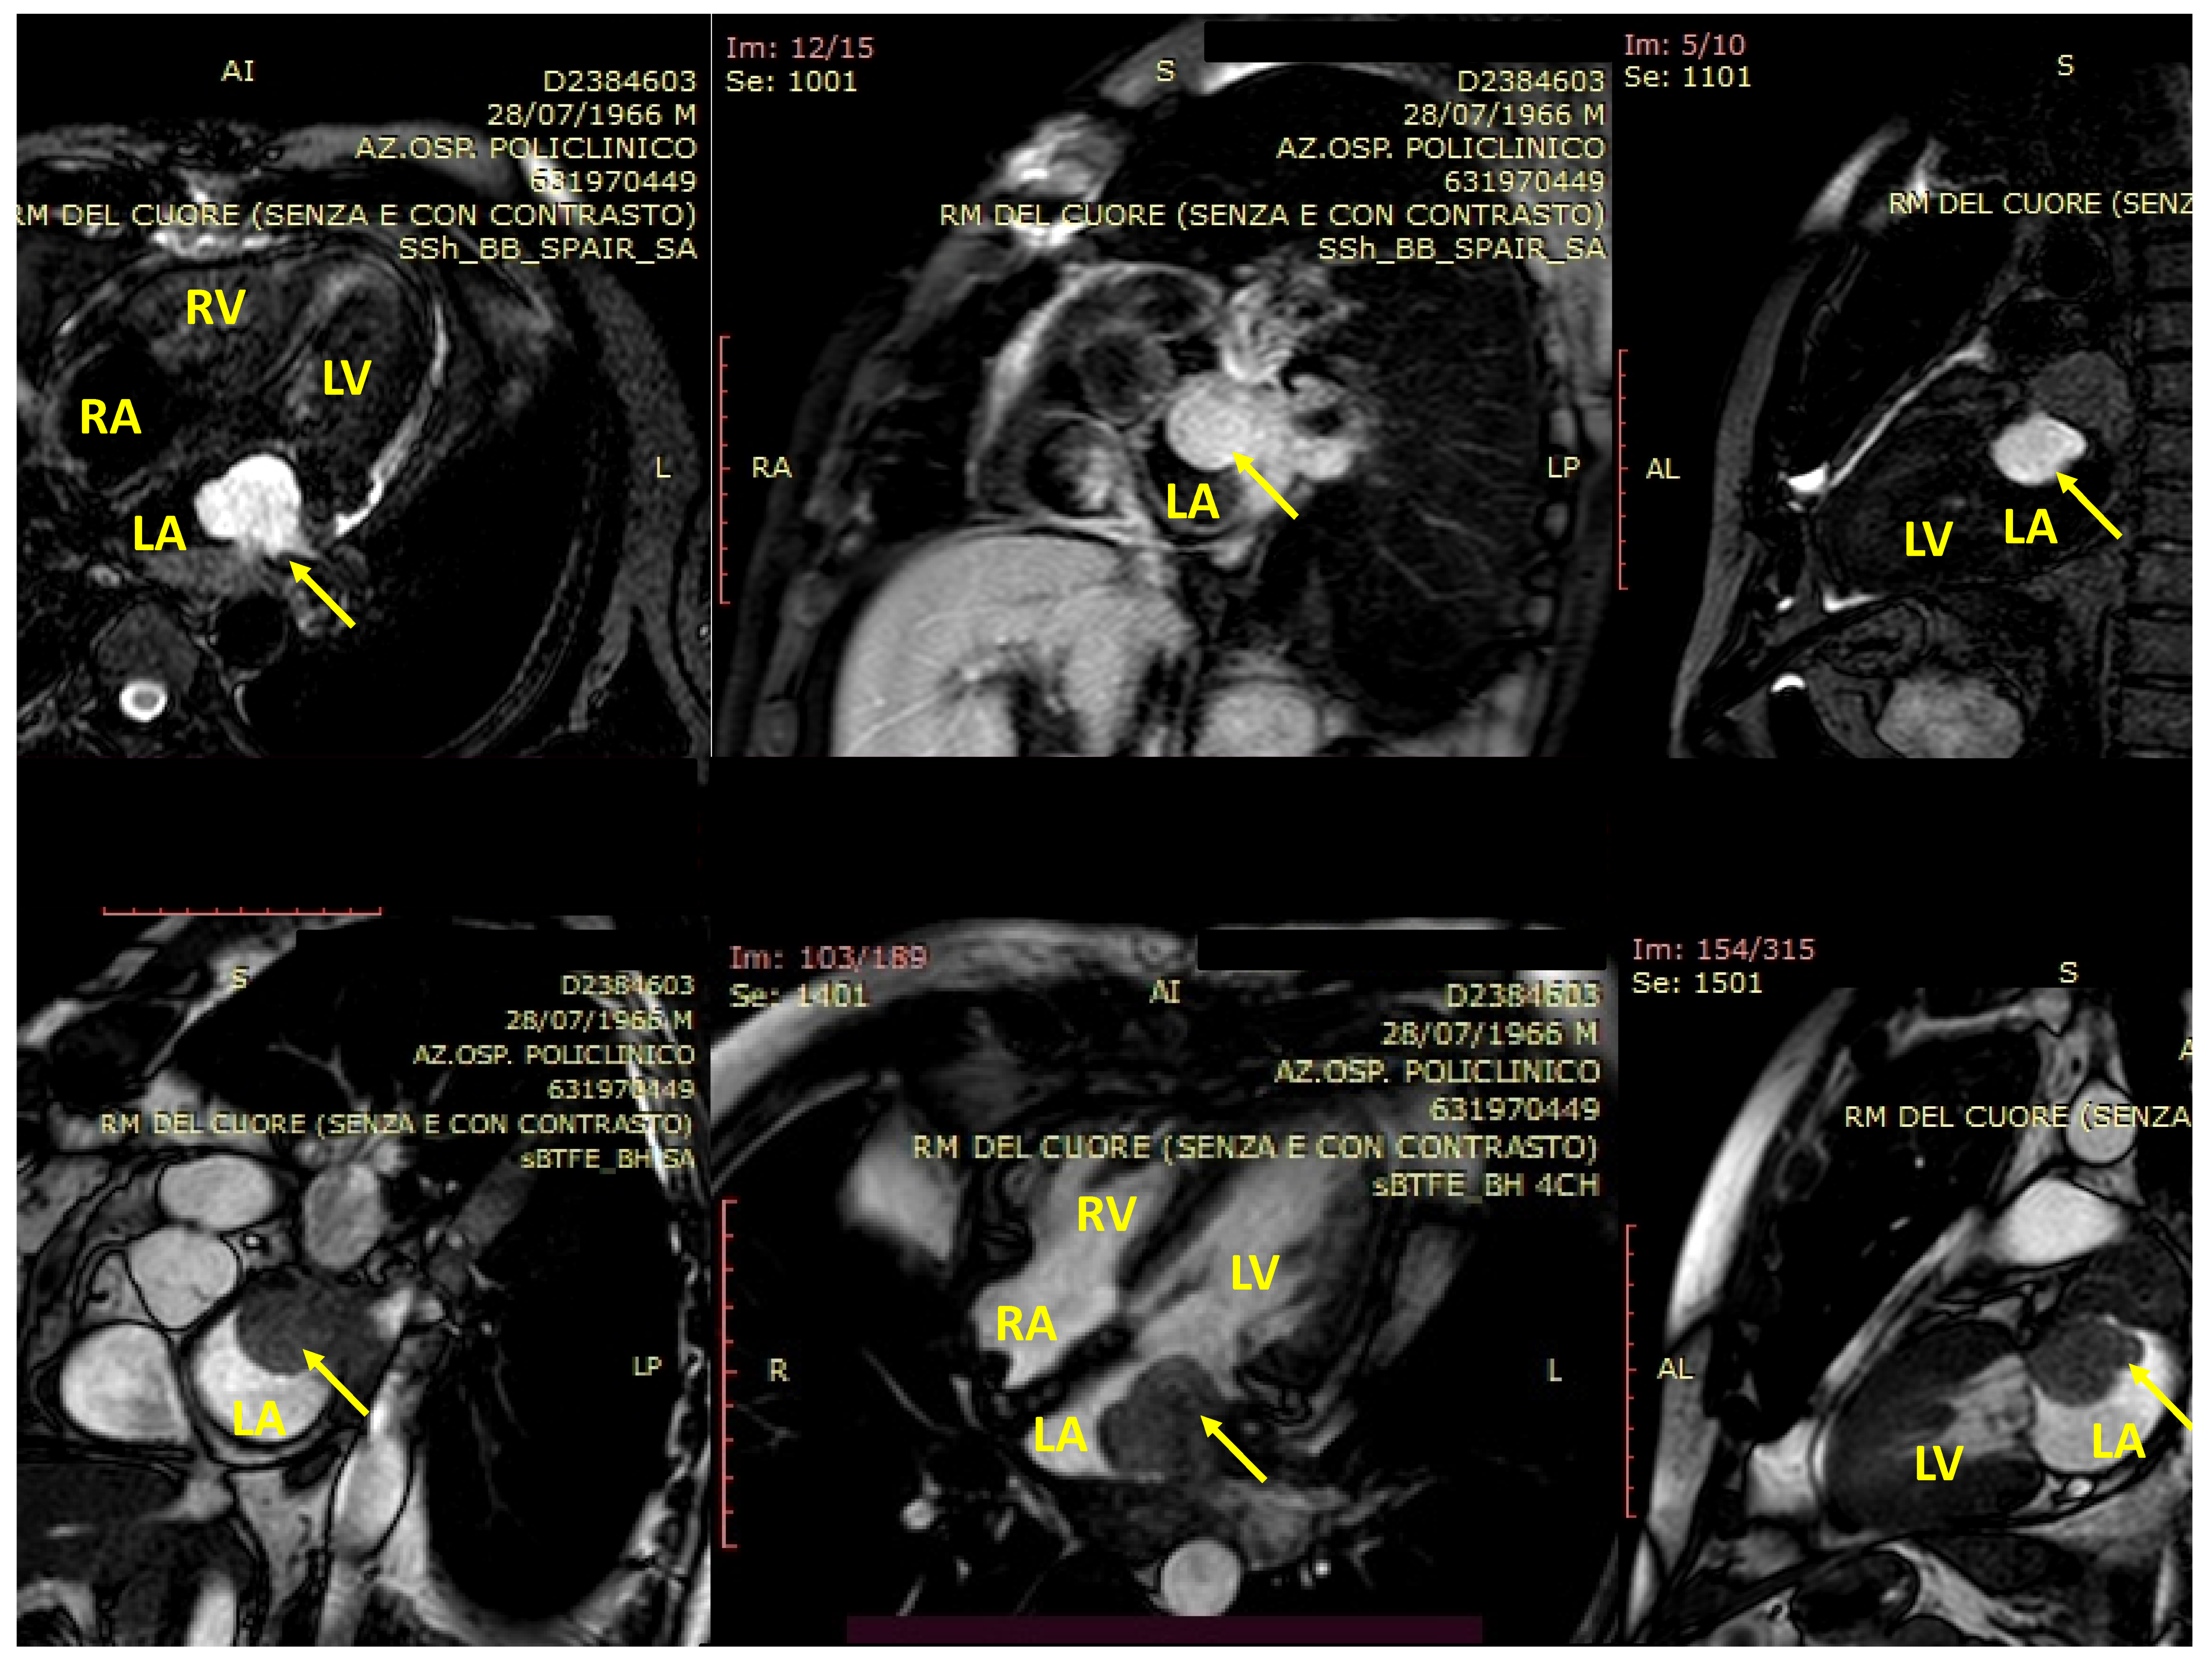

4. cMRI in pSTS-h